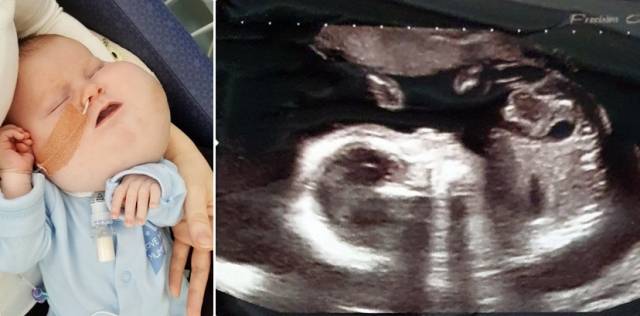

알렉스는 얼굴과 기도가 액체로 가득 차는 낭포성 림프관종을 갖고 태어났다. 싱글맘인 알렉스의 엄마 에밀리(35)는 “임신하고 20주 정도 됐을 때 초음파를 통해 알렉스의 질환에 대해 알게 됐다”며 “알렉스가 태어나기도 전부터 아이가 어떻게 생겼을지 두려웠다”고 고백했다.

하지만 에밀리는 막상 알렉스를 처음으로 본 순간 걱정했던 것과 달리 너무 예뻐서 눈물이 났다고 회상했다.

알렉스는 태어나자마자 6개월을 병원에서 보냈고 생애 첫 낭종 제거 수술을 받았다. 이후에도 수차례 제거 수술을 받았지만 낭종은 점점 커졌다. 알렉스는 낭종 무게 탓에 제대로 균형을 잡을 수 없는 상태에 이르렀다. 혼자 서 있기도 어려웠고 걷는 것 역시 불가능했다.